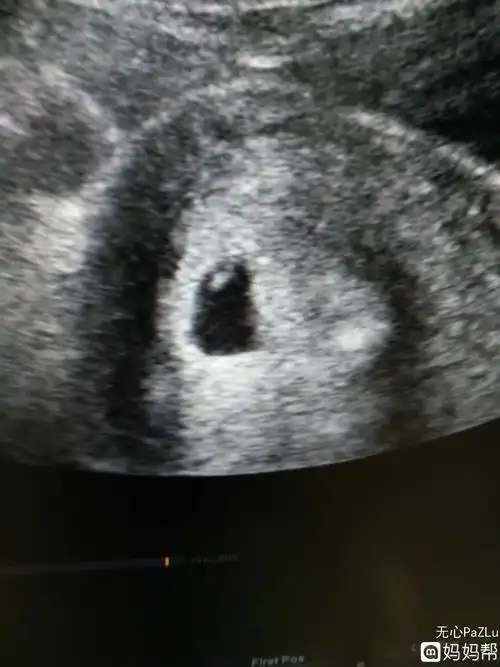

怀孕七周,今天做b超,检测胎心胎芽没问题,小肚子一侧疼,昨天下午开始

宝宝有胎心胎芽了